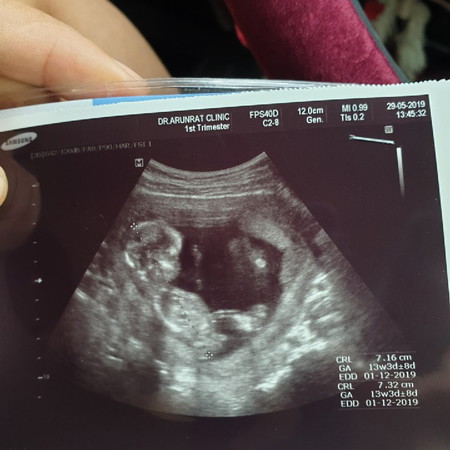

ตอนนี้ได้ตั้งท้องจะ4เดือน แต่ยังไม่รู้เพศเลยค่ะ

บ้านไหนตั้งท้องได้4เดือนแล้วค่ะ เหนเพศกันยังค่ะ

ท้อง16week2day เพิ่งไปอัลตร้าซาว์มาวันนี้ยังไม่เห็นเหมือนกันค่ะ

หมอเห็นแต่แวบๆเหมือนคอเต่าหมอเลยเดาว่าน่าจะได้ลูกชายจ้า

บ้านนี้ 18 สัปดาห์ เจอเพศเลยคะ หมอบอก ผู้ชายร้อยเปอร์เซ็นต์

บ้านนี้ซาวด์ตอน22วีคค่ะหมอบอกเห็นเพศชัดเจนดีค่ะได้ผู้ชาย

15สัปดาห์6วันรู้เพศแล้วค่ะ ถ้าผู้ชายจะรู้เพศเร็วค่ะแม่ๆ

หมอบอกผู้ชายจ้า แต่เดือนหน้าซาวซ้ำใหม่ เพื่อความชัดเจน